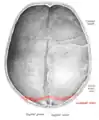

![]() Lambdoid suture (labeled at bottom right) | |

The lambdoid suture, or lambdoidal suture, is a dense, fibrous connective tissue joint on the posterior aspect of the skull that connects the parietal bones with the occipital bone. It is continuous with the occipitomastoid suture.

The lambdoid suture is between the paired parietal bones and the occipital bone of the skull. It runs from the asterion on each side.